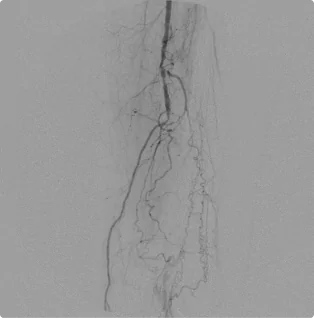

Female – Age 78

Referred by her Podiatrist for Severe Calf Pain, Non-Healing Wounds and Absent Toe Pulses

This patient had already been told by a different vascular specialist that there was nothing that they could do for her severe pain. The blockages in the arteries in her legs were so severe, no pulse could be felt in her toes. After ultrasound and evaluation, Dr. Goldstein concluded intervention was possible. Using advanced interventional techniques, He successfully cleared her arteries in both legs. Her pain subsided and her wounds healed over time. The team at Pedes Orange County regularly monitors her arterial flow to ensure she remains pain and ulcer-free.

Before

Arterial flow through the right knee and into the calf before intervention. The blockages below the knee are so severe that no clear flow exists down into the toes, causing severe pain as the muscles and tissue starve of blood.

After

After working to clear the blockages from both sides, Dr. Goldstein establishes flow through the two lower branches of the arteries, allowing blood to flow down into the foot.